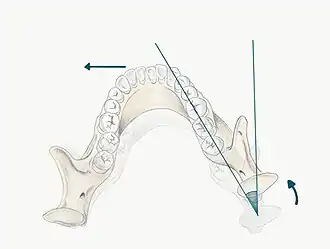

It is important to define the movement of the condyles in lateral excursions:

- Working condyle: This is the condyle closest to the side which the mandible is moving (e.g. if the mandible moves laterally to the right, the right condyle is the working side condyle)

- Non-working condyle: This is the side to which the mandible is moving away from (e.g. if the mandible moves laterally to the right, the left condyle is the non-working side condyle)

- The maximum lateral movement of the mandible to the left or right side is approximately 10-12mm[2]

- The primary movement in lateral excursions occurs on the non-working side (NWS) condyle (also called the balancing or orbiting condyle). The NWS condylar head moves in a downward, forward and medial direction. This movement is defined against two separate planes, the vertical and horizontal plane

- Bennet Angle : the angle of medial movement on NWS condyle relative to the vertical plane

- Condylar Angle : the angle of downwards movement of the NWS condyle relative to the horizontal plane

- The working side (WS) condyle (also called the rotating condyle) undergoes an immediate, non-progressive lateral shift. This movement is called the Bennet movement (however this may be confused with the Bennet Angle), so this is more commonly referred to as an Immediate Side Shift. The condyle is seen to rotate with a slight lateral shift in the direction of movement[6]